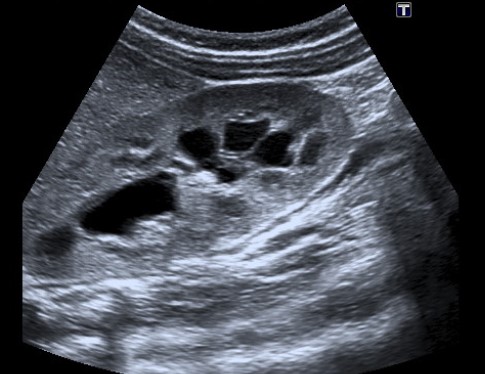

A su llegada a Urgencias, se realiza radiografía de abdomen sin alteraciones y ecografía abdominal en la que se objetiva dilatación uretero-pielo-calicial bilateral (Fig. 1) además de distensión vesical con nivel líquido-sedimento y discreto engrosamiento de pared (Fig. 2).

Figura 1. Dilatación uretero-pielo-calicial